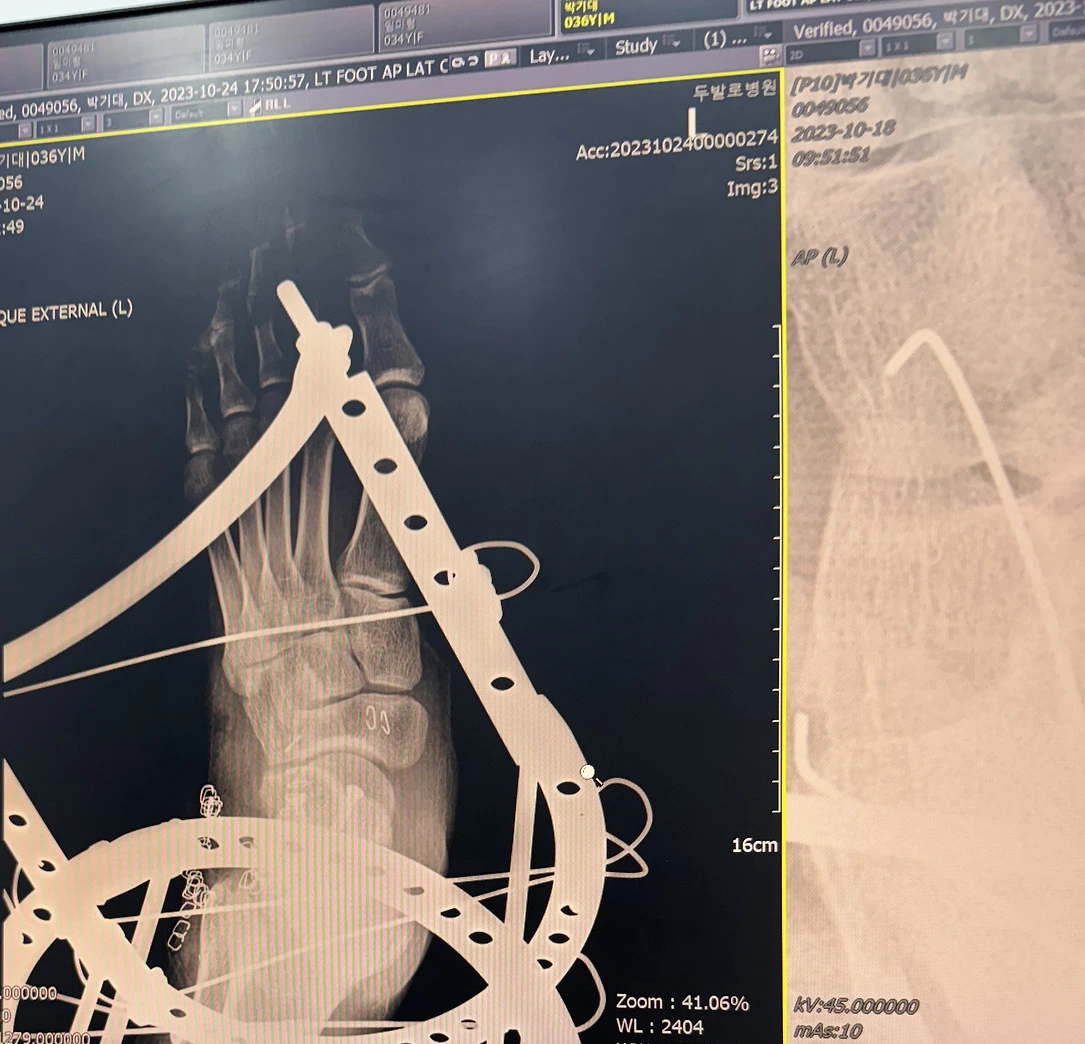

철제 외고정기를 다리에 박는 수술을 한지도 2주가 지났다. 그동안 1주에 한 번씩 아버지가 나를 병원에 데리고 가 소독과 재활을 받도록 해주셨다. 말 그대로 철사 보형물이 정강이와 발에 박혀있었기 때문에 이 부분의 살이 짓무르지 않도록 주기적으로 소독을 하며 잘 관리해 주어야 했다. 남양주와 압구정은 가까운 거리가 아님에도 불구하고 아버지는 병원 가는 날을 빠트리는 법이 없었다.

외고정기를 찬 발은 씻을 수가 없어서 각질과 수술할 때 묻었던 피로 범벅이 된 채 철제 보형물이 박혀있는 부분만 소독을 했다. 병원에 방문할 때마다 장갑을 끼고 외고정기를 차고있는 발을 마사지해 주었던 물리치료사에게 미안한 마음이 들었다. 마사지를 받고 나면 좀 편안했긴 했지만 많이 효과가 있는 것 같지는 않았다.

절제 외고정기를 차고 2주 차 되는 날 의사 선생님이 외고정기를 제거하는 수술 날짜를 잡아주셨다. 예전에는 발목의 뼈가 이상이 있으면 고정해 안정적으로 붙을 때까지 최대한 움직이지 않게 했다고 한다. 하지만 최근 수술 트렌드는 발목을 오래 못 움직이게 하면 후유증으로 발목의 움직임 각도가 잘 안 나오는 경우가 많기 때문에 뼈가 붙는 시기를 잘 계산해서 발목을 고정해 놓는다고 한다.

나는 거골이 완전히 박살 났기 때문에 이런 최신 수술트렌드는 나에게 적용하기 어려웠다. 뼈에 금이 가거나 경미한 부상은 1~2주 정도 깁스를 하는 반면 나는 4 동안 발목을 움직이지 않게 고정해야 했다. 거골의 특성상 뼈가 붙지 않아 함몰이 될 가능성이 있고, 이것은 최악의 상황이기 때문에 의사 선생님의 처방인 제일 탄탄하게 고정할 수 있는 철제 외고정기를 4주간 착용하는 것은 최선이었을 것이다. 하지만 모든 수술이 끝나고 어떤 후유증이 있을지는 누구도 예측하지 못했다. 의사 선생님도 수술 후 발을 디뎌 봐야 알 수 있을 것이라고 했다.

의사 선생님은 외고정기 제거 수술은 이전 수술보다 간단한 수술이라고 했다. 이전의 뼈에 나사를 박고 인공뼈와 나의 골반에서 추출한 뼈를 이식해서 원래뼈의 모양을 구현하는 수술은 6시간 정도 걸렸다. 반면 이번 수술은 1시간 내외로 수술시간도 짧았다.